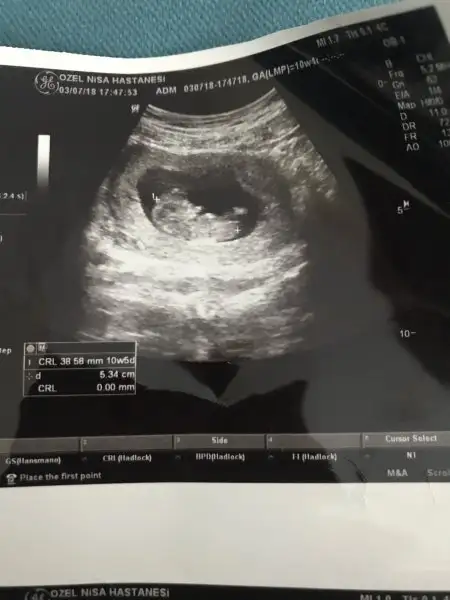

Ben de her iki sonuca da sevinmeye hazırlamıştım kendimi. Dedigin gibi sagkikli sihhatli olsunlar evlat evlat sonucta...Bende erkek hissediyorum ama pek dile getirmiyorum.Eşiminde gönlünden erkek geçiyor biliyorum ama kızımız olursa da çok sevinirim.Sağlıklı olsunlarda